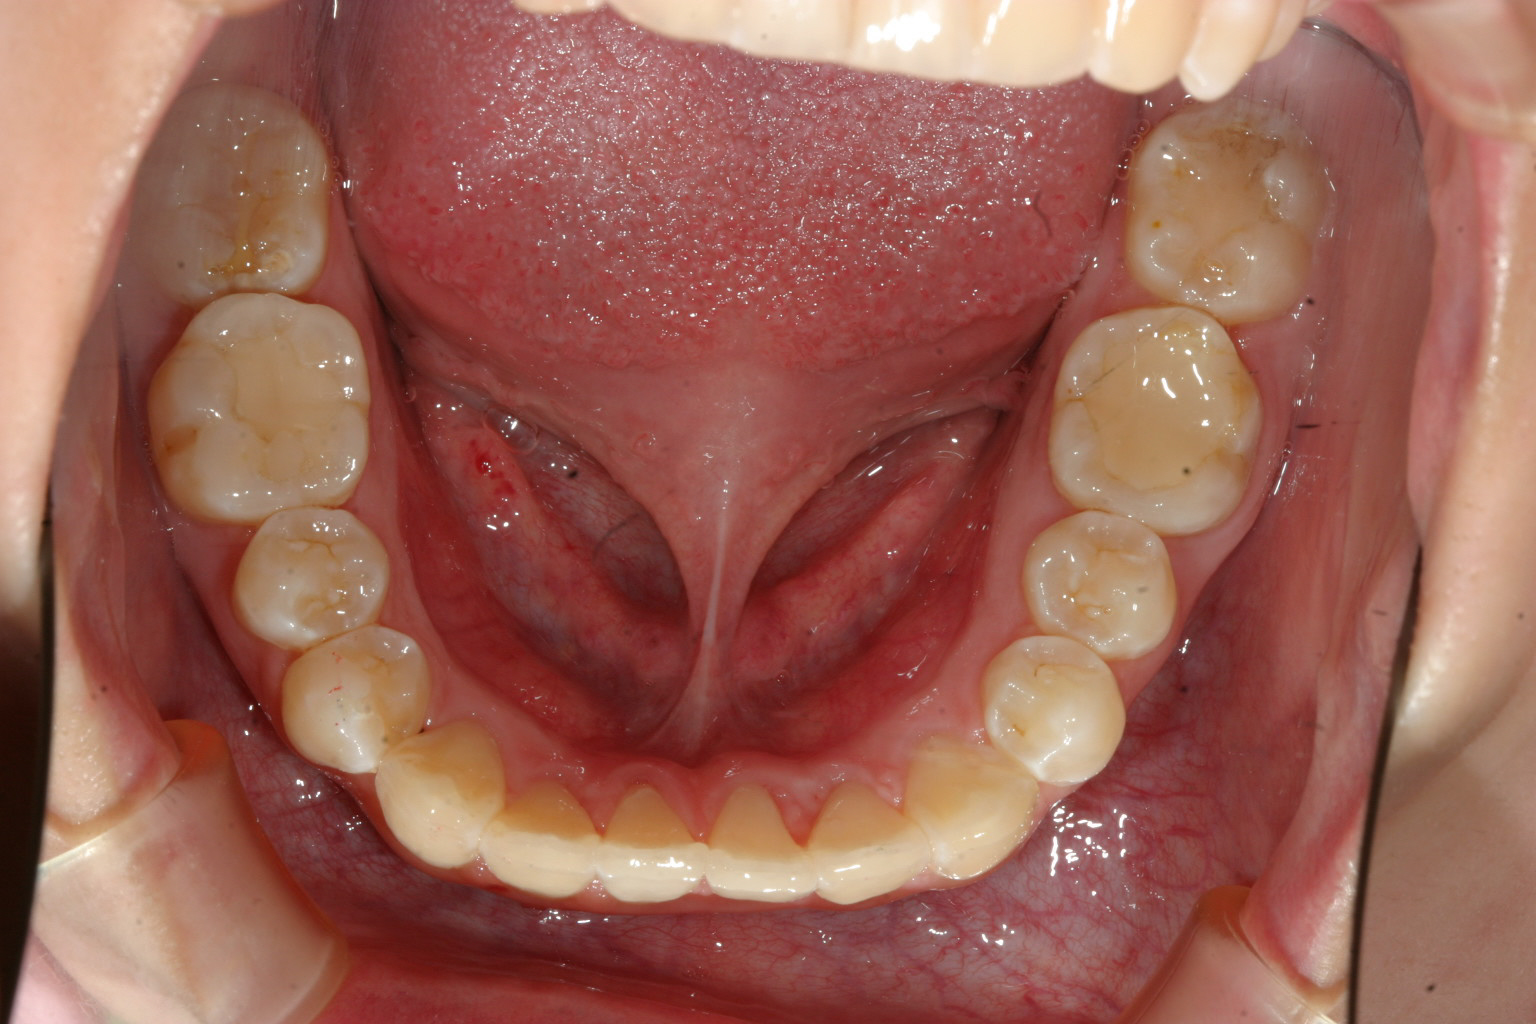

抜歯無しでここまで改善致しました。

下顎のガタガタも綺麗になりました。

このケースは非抜歯で犬歯の唇側転移を改善致しました。

下顎も結構ガタガタしてましたが患者様の熱心な頑張りで僅か1年4カ月でこの様に綺麗に改善しました。

インビザラインは上手く治らないとおっしゃる患者様も居られるようですが患者様の頑張り次第でここまで改善できると言う証明です。

当院で過去17年間で7700症例近くインビザラインで治療行いましたが97%の患者様でいい結果を出して頂いています。